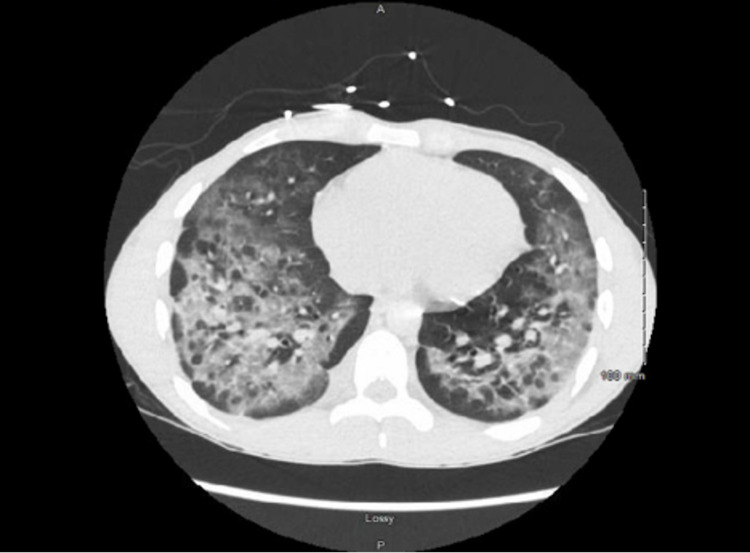

Acute hypoxemic respiratory failure (AHRF) acutely worsened while on empiric therapy for CAP requiring a high flow nasal cannula (HFNC) with 35 to 45 L/min O2 and 0.4 to 0.6 FiO2, and he was started on treatment with methylprednisolone 40 mg every six hours and albuterol-ipratropium nebulizers. Infectious disease and pulmonology were consulted. Work up with CT chest demonstrated diffuse bilateral lower lobe predominant ground-glass opacities with relative sparing of the subpleural regions and associated interstitial thickening (Figure 2). Suspicion of COVID infection remained high but he had a few more negative tests. An echocardiogram showed normal size lateral ventricles and normal systolic function with an ejection fraction of 63%; left pleural effusion was noted. AHRF improved significantly to 2L of nasal cannula after two days of receiving methylprednisolone. The patient was diagnosed with EVALI as a diagnosis of exclusion and AHRF resolved with steroid therapy.

Reaching the diagnosis of EVALI could be challenging for it is a diagnosis of exclusion, and CT findings could provide some clues. Ground glass opacities are the most common presentation of EVALI, with multifocal distribution and sub-pleural sparing in about half of the patients [ref. 13]. Sub-pleural sparing was seen in our patient, and this finding is unique for sub-pleural sparing has not been noted in COVID infection, which usually presents as consolidation, crazy-paving pattern, and subpleural line opacities. Recognizing subpleural sparing patterns on imaging could point towards the diagnosis of EVALI rather than COVID infection if repeat COVID testing and BAL sample from bronchoscopy are both negative [ref. 14].